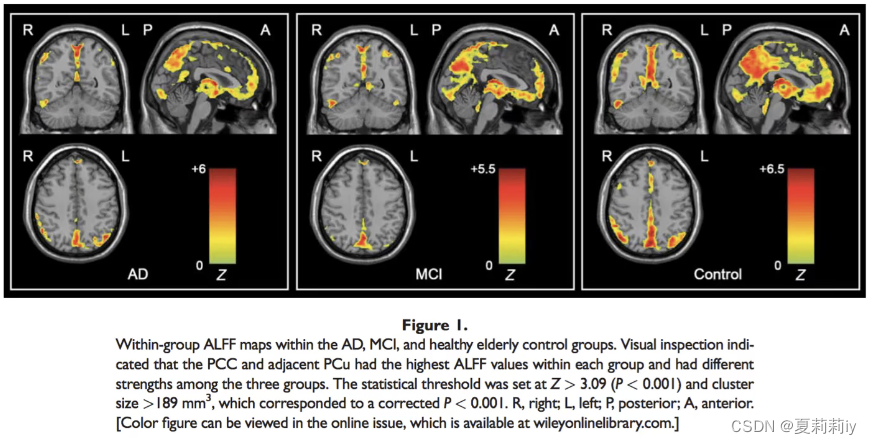

①可以看看患者和普通人ALFF的图像差异

③生成的结果示例

①有三组的时候就需要ANOVA,即推断三组之间有两组具有显著差异,避免多重比较

②可以直接做ANOVA,也可以在做的时候先做多重比较矫正。看结果可以用Z值